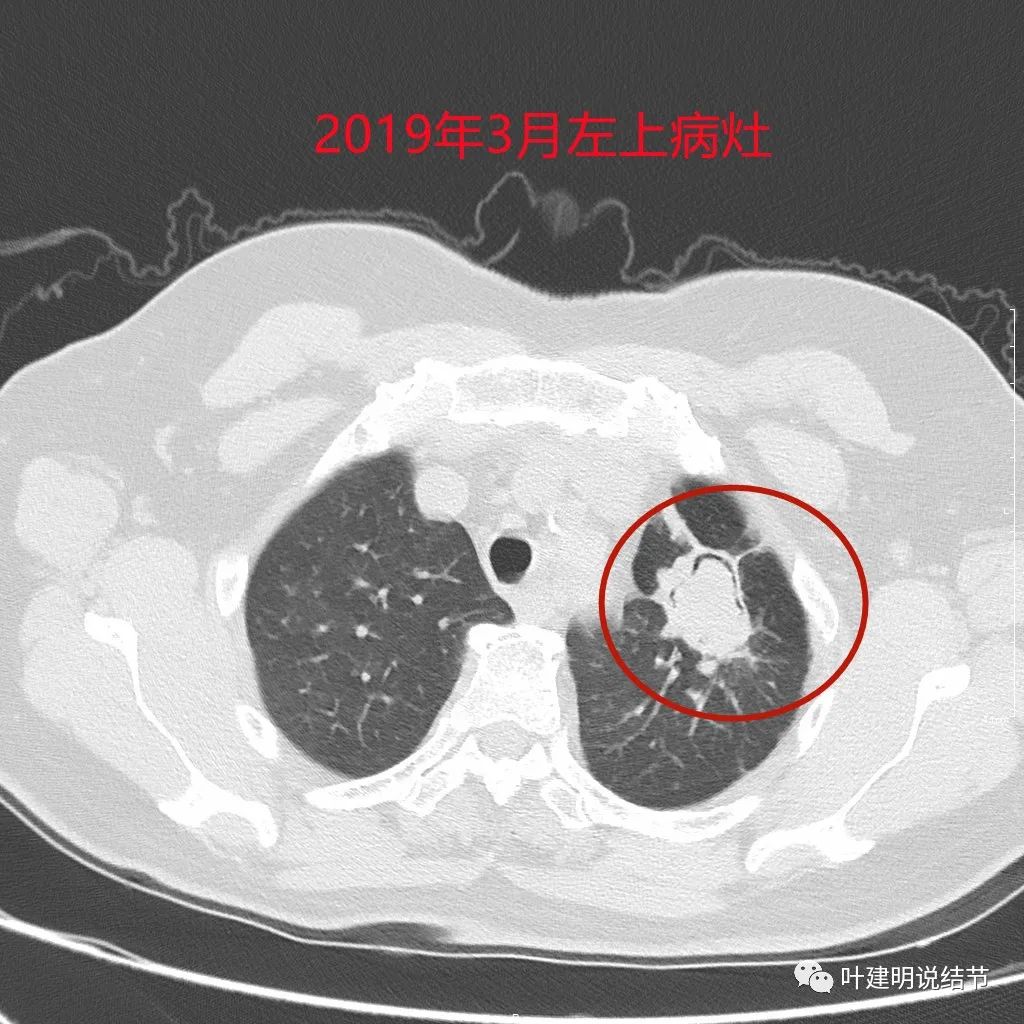

金华的某A,女性,今年61岁,在近2年半前曾在左肺下叶肺癌以及左肺上叶挺大的支气管囊肿伴囊内真菌感染进行了“左肺下叶切除+左肺上叶部分切除(因病灶大且位置靠中间,基本切除了绝大部分固有段)+纵隔淋巴结清扫术”。我们先来看当时的左侧病灶:

上图是左上叶的病灶,有4-5厘米左右,而且位置挺靠中间,但因为左下叶是肺癌,恶性的,已经要切肺叶,则上叶不能行叶切,虽做了大的楔切,其实范围基本上与固有段类似了,所以留下的只有舌段那么一点点,而且因上部与下部都肺组织被切除,术后左肺留下的那点膨胀也差,术后胸闷气促明显,伴喘憋,恢复很慢。